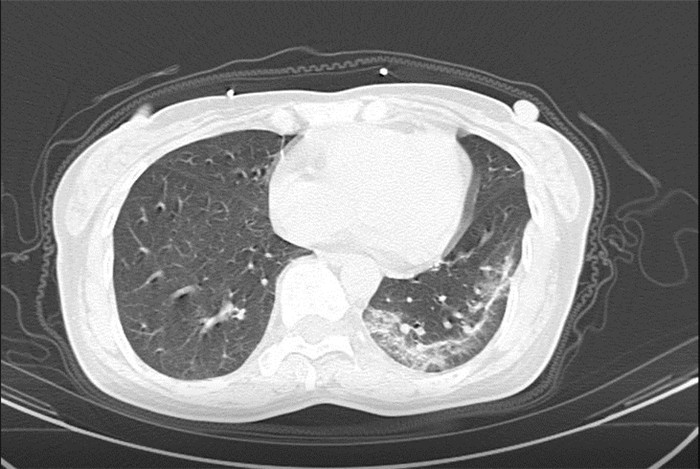

CT為當前首選篩查與診斷的主要影像學手段,胸部CT的病毒性肺炎檢出率高。

方舟CT(CT Ark)可以滿足全面的臨床功能,配置16層、32層、64層、128層CT,實現了低劑量掃描要求,配合NDI微劑量迭代技術,智能毫安調控技術,使各種場合下、各部位低劑量掃描得以實現;超高分辨率CT病灶靶掃描,使病灶的密度顯示更加精確,能夠顯示病灶內輕度的密度變化,有利于小病灶的密度定量分析和及時診斷。